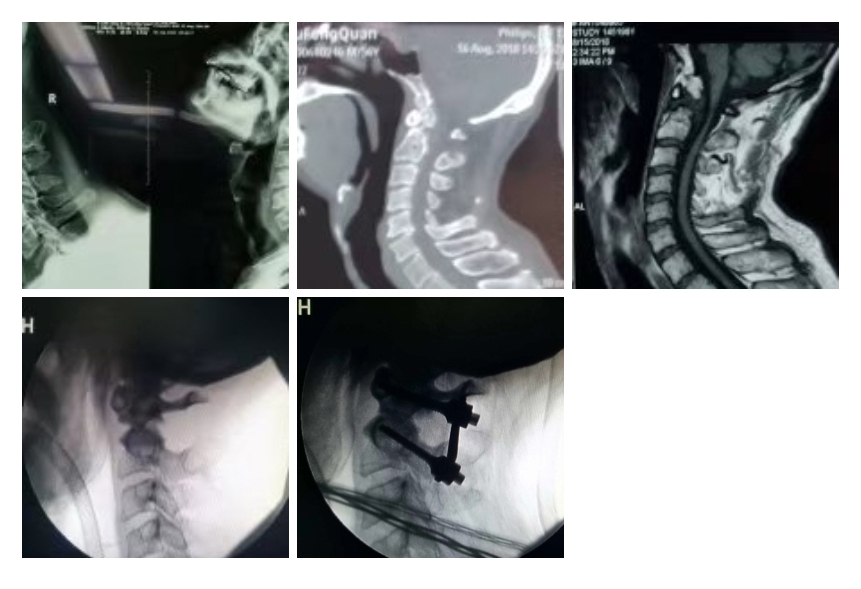

典型病例一: 经典“后路寰枢侧块钉板固定植骨融合术”

齿突不连,寰枢关节很不稳定。当仰头时寰椎后弓与枢椎棘突碰撞,寰椎后结节变形,呈假关节样貌(图1)。枢椎后有软组织团块,是被拉长的后纵韧带在寰枢关节对位正常时松弛、堆积所致(图3)。术中用颅骨牵引维持寰枢关节的对位(图4),实施后路寰枢侧块钉板固定植骨融合术。选用合适长度的固定板,做恰当的预弯曲度,将寰椎固定在水平位。